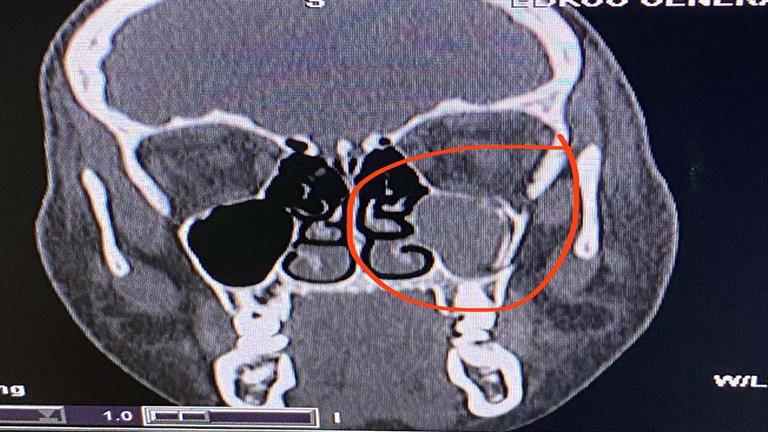

أجرى فريق طبي، من قسم جراحة الوجه والفكين والتجميل، بمستشفى ادكو المركزي عملية جراحية متقدمة ناجحة لطفلة عمرها 15 عاما إثر سقوطها من الطابق الرابع.

وتضمنت العملية إصلاح كسر في الوجه، وكسر مجمع في عظم قاع العين وعظم الخد باستخدام جرح تجميلي من داخل جفن العين وتثبيت الكسر بشرائح صغيرة من دون احداث جروح خارجية بالوجه.

أجريت الجراحة باشراف مدير المستشفى واستشاري جراحات التجميل الدكتور أحمد حمدي خضر، أخصائي جراحة الوجه والفكين والدكتور محمد جلال الديب ، وبمساعدة الدكتور ضياء ياسين .